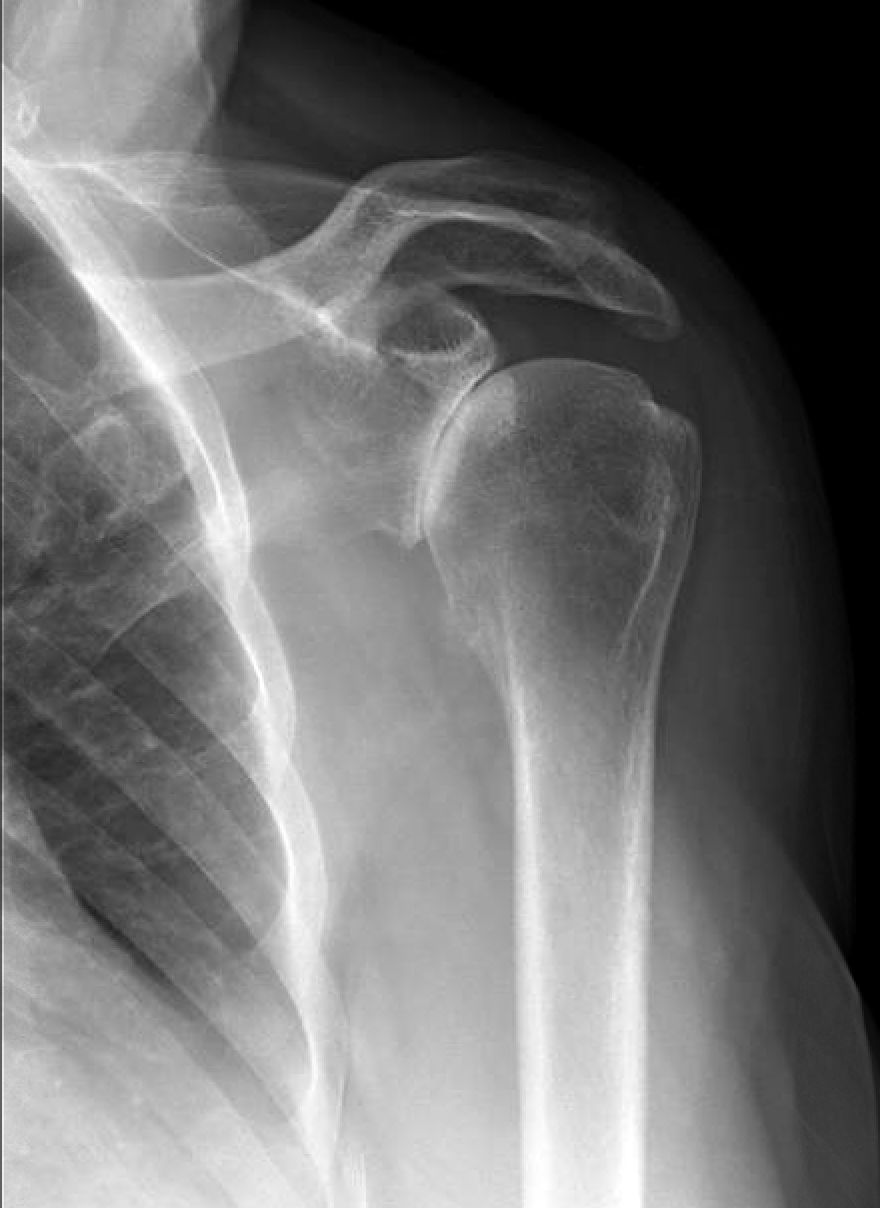

Xray findings one year after the surgery. A) Anterior posterior view

Xray findings one year after the surgery. A) Anterior posterior view After Humerus Surgery Physio Learn about the types of surgery and recovery after proximal humerus (upper arm) fractures, which are common injuries that may require. If you have surgery, you likely will begin physical. After a humerus fracture, your ability to move your shoulder, called range of motion , will be limited. Physical therapy after a proximal humerus fracture is crucial to restore the. After Humerus Surgery Physio.